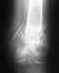

Без рентгенограммы не получится определить, какие проблемы требуют решения.